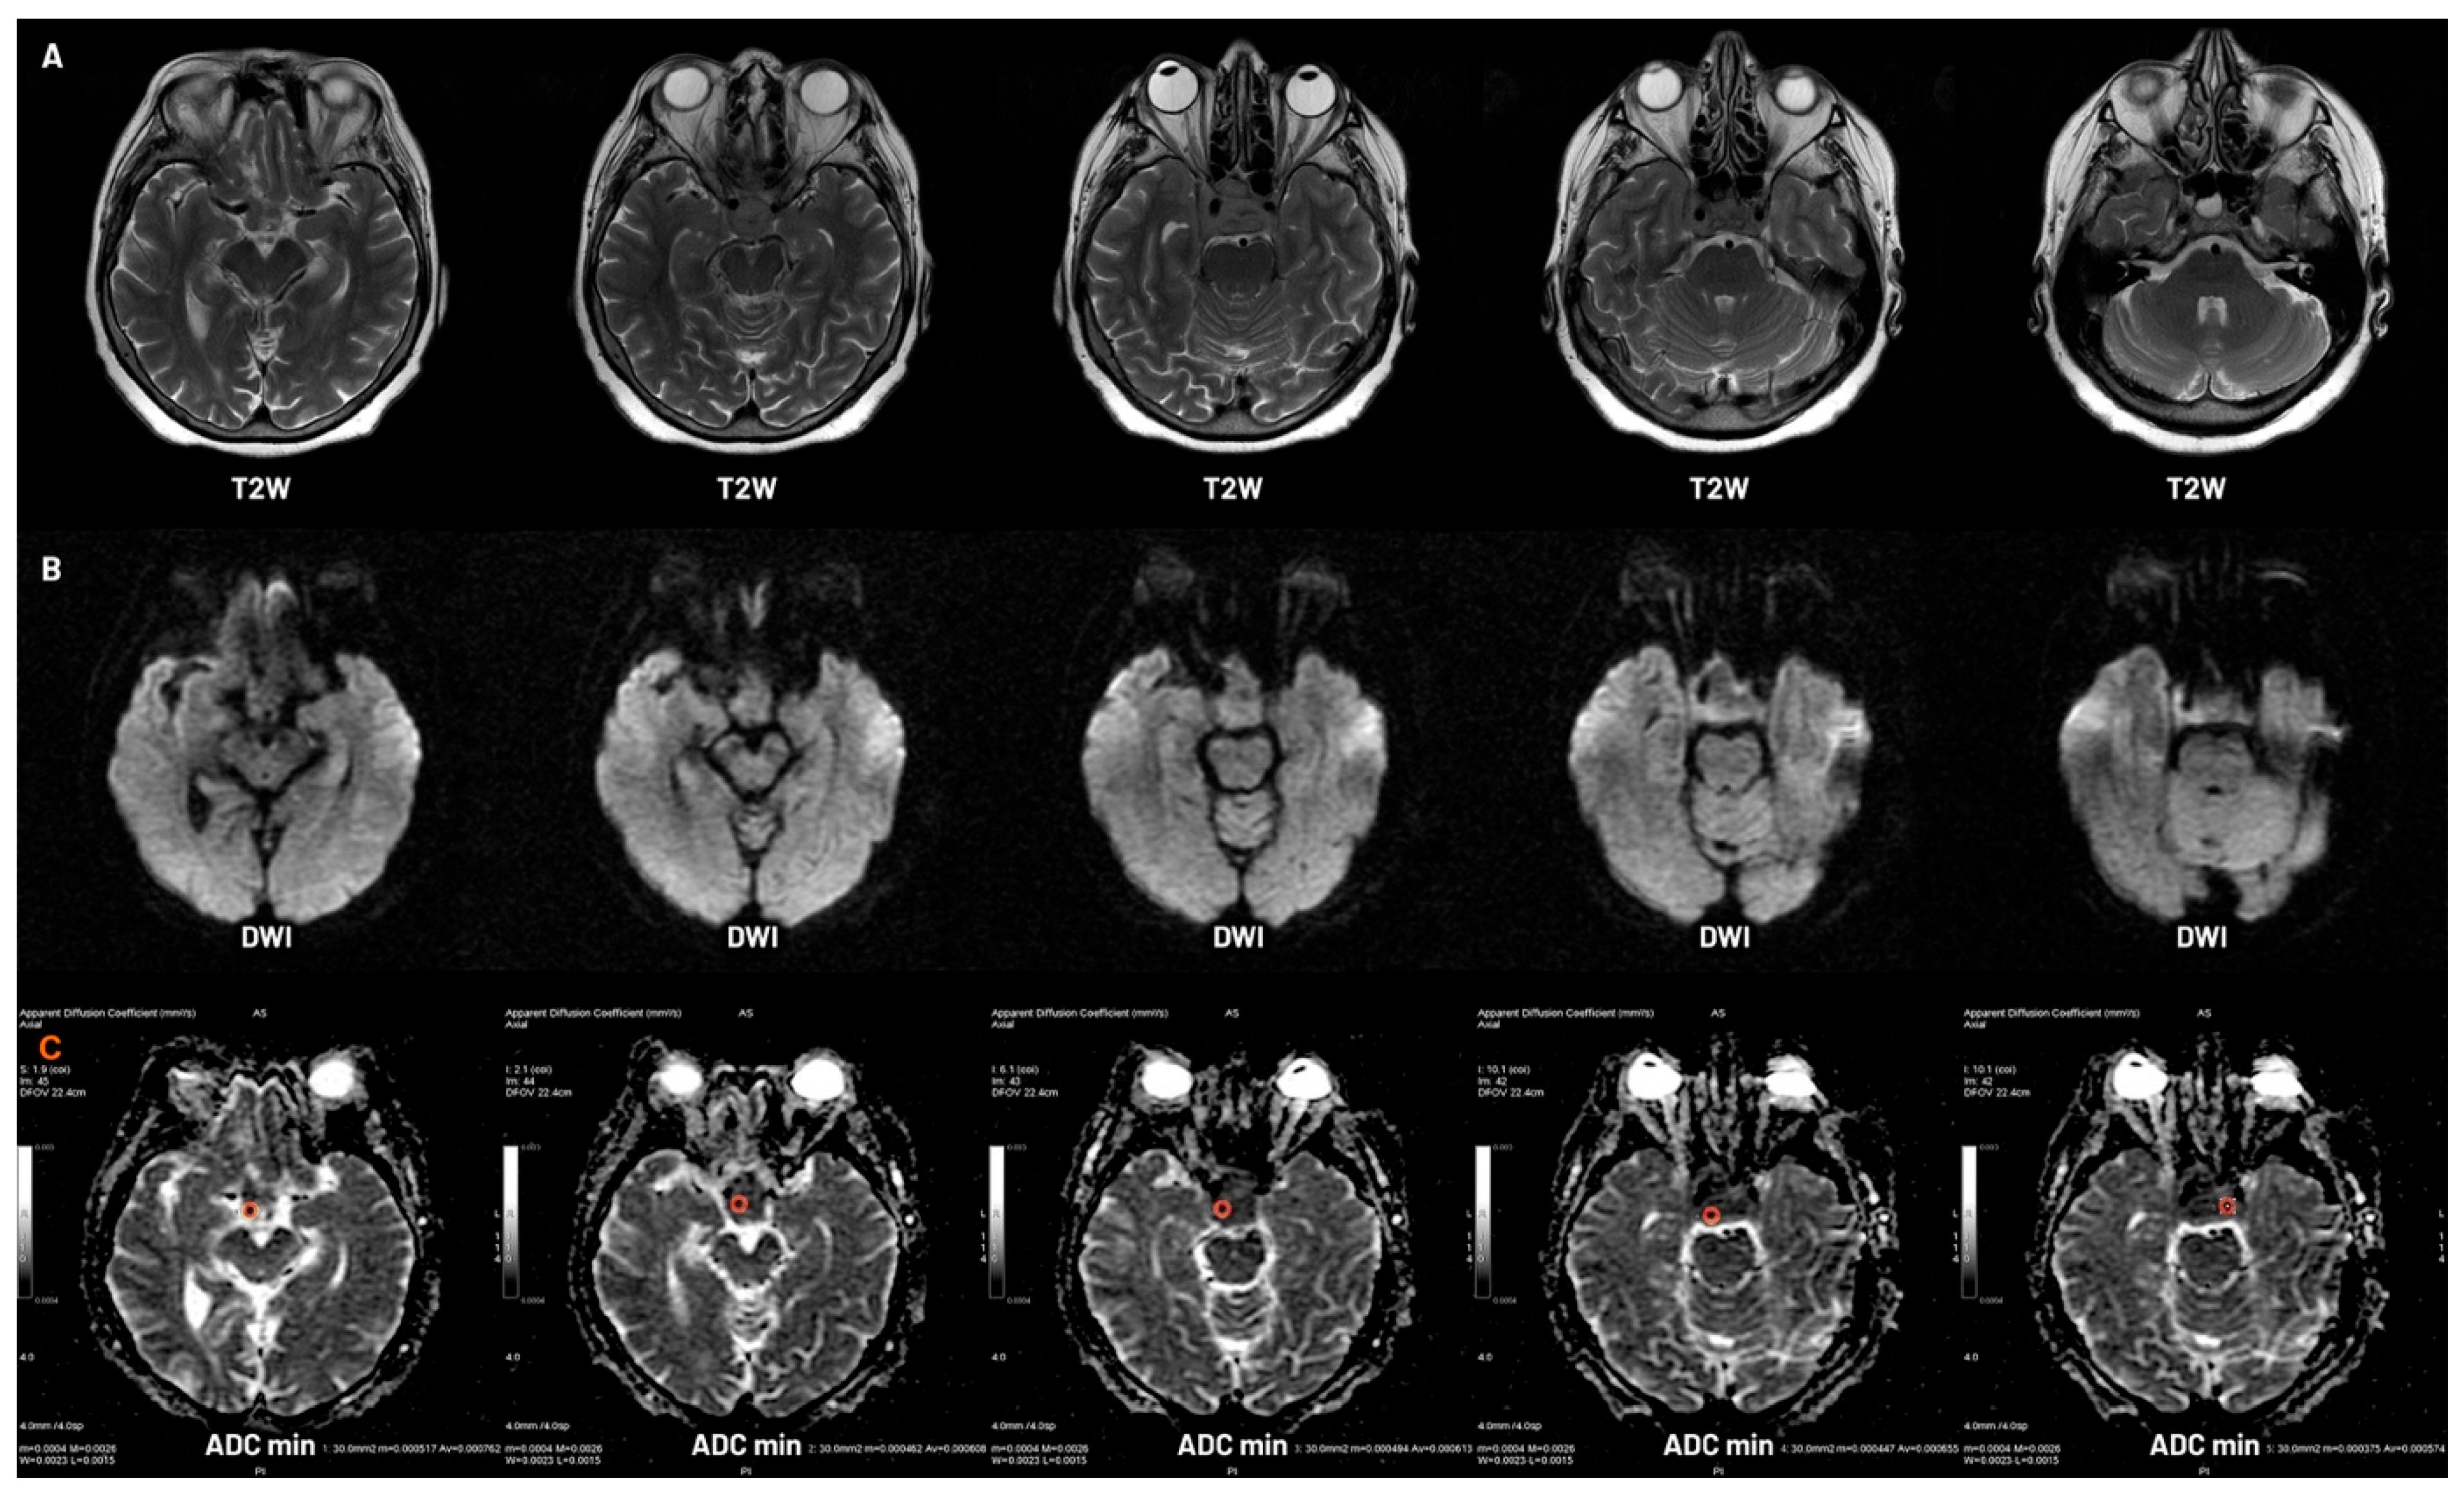

- Korbecki, A.; Wagel, J.; Zacharzewska-Gondek, A.; Gewald, M.; Korbecka, J.; Sobański, M.; Kacała, A.; Zdanowicz-Ratajczyk, A.; Kaczorowski, M.; Hałoń, A.; et al. Role of Diffusion-Weighted Imaging in the Diagnosis of Pituitary Region Tumors. Neuroradiology 2025, 67, 437–447. [Google Scholar] [CrossRef]